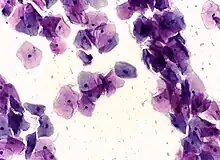

In a typical scenario, about 0.5% of Pap results are high-grade SIL (HSIL), and less than 0.5% of results indicate cancer; 0.2 to 0.8% of results indicate Atypical Glandular Cells of Undetermined Significance (AGC-NOS).

- High-grade squamous intraepithelial lesion (HGSIL or HSIL)

Micrograph of a normal pap smear

Micrograph of a Pap test showing a low-grade intraepithelial lesion (LSIL) and benign endocervical mucosa. Pap stain.